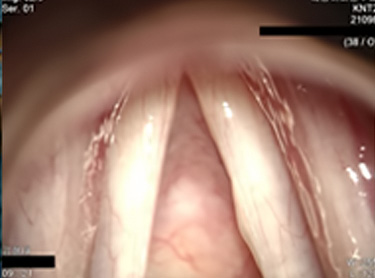

수술 전 성대